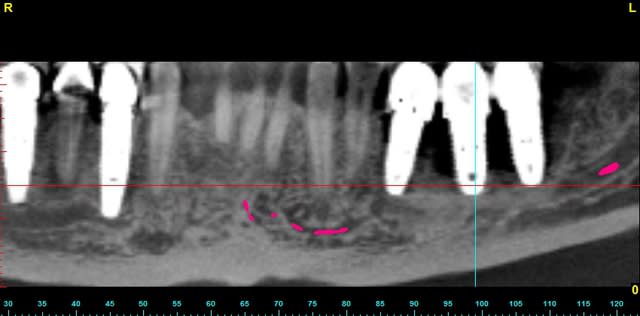

le cas n'est déjà pas facile...

il faut explanter tous le secteur 3 et 4

mais quid de la gestion osseuse ?